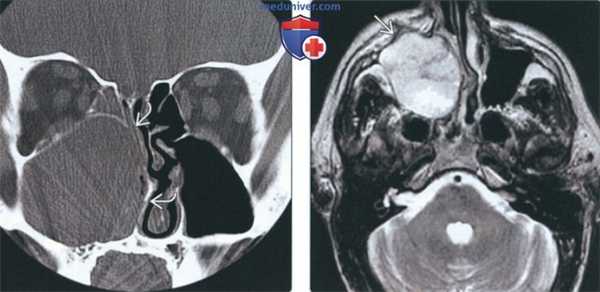

(Слева) На корональной КТ в костном окне определяется снижение пневматизации правой верхнечелюстной пазухи, обусловленное большим экспансивным АКР. Внутренняя стенка верхнечелюстной пазухи разрушена; объемное образование распространяется в полость носа. Обратите внимание на отклонение носовой перегородки влево.

(Справа) На аксиальной МРТ (Т2ВИ) у этого же пациента визуализируется объемное образование с неоднородным сигналом во всех отделах, минимально распространяющееся в предчелюстные мягкие ткани. Четкие края опухоли позволяют предположить более низкую степень злокачеавенности АКР.